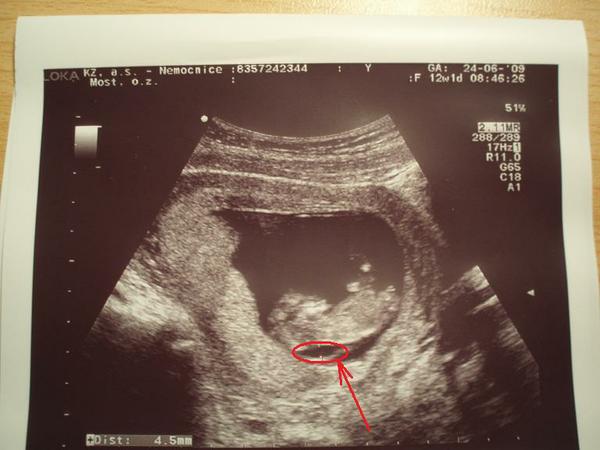

@ivcula7 ve 4 a 5 měsíci je mimčo už velké, to pak se dělá klasickým porodem. ALe nešil. Vždyt ještě nemáš nic potvrzené. 4etla jsi celou diskuzi? já jsem tu jeden čas sepisovala všechny výsledky. zkusím najít poslední soupis. Jo a hodím ti sem foto naší Adélky, kde je vidět jak měla prosáknutí v záhlaví, neboli velké šíjové projasnění, neboli NT. Ne jednom vidíš dole údaj dokonce 5mm. to je délkamezi těmi dvěma body na fotce, jak to doktor měřil. Něco takového viděl i u tebe, že?

@klara.t : NT 4,6, nosní kůstka přítomna, odběr chor.klků - genetika v pořádku, krev v pořádku, UTZ v 16. týdnu v pořádku, velký UTZ v 20.týdnu v pořádku - holčička , kardiologie-podezření na nedomykavost trojcípé chlopně, ale málo významné, na další kontole - srdíčko se umoudřilo, nedomykavost se sama spravila, UTZ v 31+1 v pořádku, 1.1. 2010 se narodila Adélka (3290g, 49cm) - zdravá a v pořádku, kontrola srdíčka - naprosto v pořádku

@lucida : NT 4,6 má zdravou holčičku

@olga777: NT=4,6 (12tt), UTZ OK

Mě tenkrát doktor říkal, že NT do 6 je v pohodě. Stejně mě neuklidnil a začala jsem pátrat na netu po informacích. A našla jsem tyto stránky a ponořila se do toho problému víc a víc (u dcery jsem ani nevěděla, že nějaké NT hodnoty existují a měla 3,5. A byl klid). U syna by mi doktor ani ty NT(4,6) hodnoty neřekl, kdybych se nezeptala. Tenkrát mě naštval a odešla jsem od něj 🙂